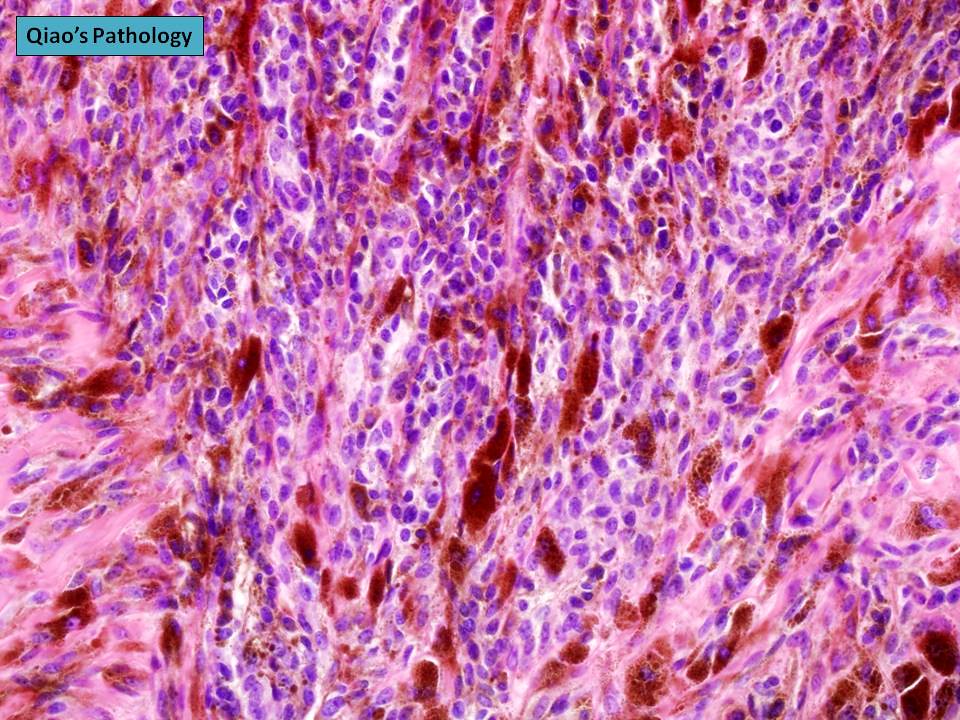

Qiao's Pathology Cellular Blue Nevus Microscopic photo sh… Flickr Cellular Blue Nevus Treatment A blue nevus is a small bluish mole that will typically last the person’s lifetime. [1] [2] [13] [14] the definitive treatment of blue nevus. The cellular blue nevus can present a diagnostic pitfall microscopically and must be distinguished from melanoma. These lesions tend to be. The cellular blue nevus is a less common lesion but often clinically similar to. Cellular Blue Nevus Treatment.